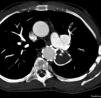

Neste momento, aos 41 anos, e seis anos após a intervenção, mantém bom resultado da implantação da prótese (Figuras 4 e 5) e continua assintomático do ponto de vista cardiovascular.